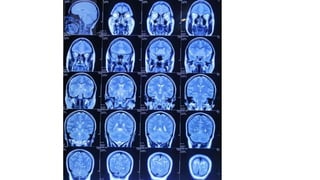

Radiological findings

• Multiplaner sagital ,coronal and axial images show a well defined ,midline, broad dural based,

lobulated T1WI iso , T2WI iso to slightly hyper and FlAIR hyperintense mass noted in suprasellar

Radiological findings • Multiplanersagital ,coronal and axial images show a well defined ,midline, broad dural based, lobulated T1WI iso , T2WI iso to slightly hyper and FlAIR hyperintense mass noted in suprasellar area having extension forwards along the planum sphenoidale and backwards along the dorsum sellae. • After IV contrast avidly homogenous enhancement of the lesion and adjacent linear dural enhancement over the clivus and planum sphenoidale representing dural tail are noted. • The lesion causing compression over the optic chiasma, pituitary gland and floor of 3rd ventricle, and encasing the supraclinoid ICA, ACA and MCA of both sides. • The mass effect is evidenced by obliteration of Suprasellar & interpeduncular cysterns and symmetrical indentation of underlying cerebral cortex. • No perilsional edema is noted • However lateral , 3rd and 4rth ventricles appear normal • Complementary CT cut was taken and showing iso to slightly hyperdense lesion. No calcification is noted. Bone CT shows bony hyperostosis at planum sphenoidale .Sellar size is within normal limit

Radiological diagnosis • Suprasellarmeningioma with planum sphenonale and dorsum sallar extension